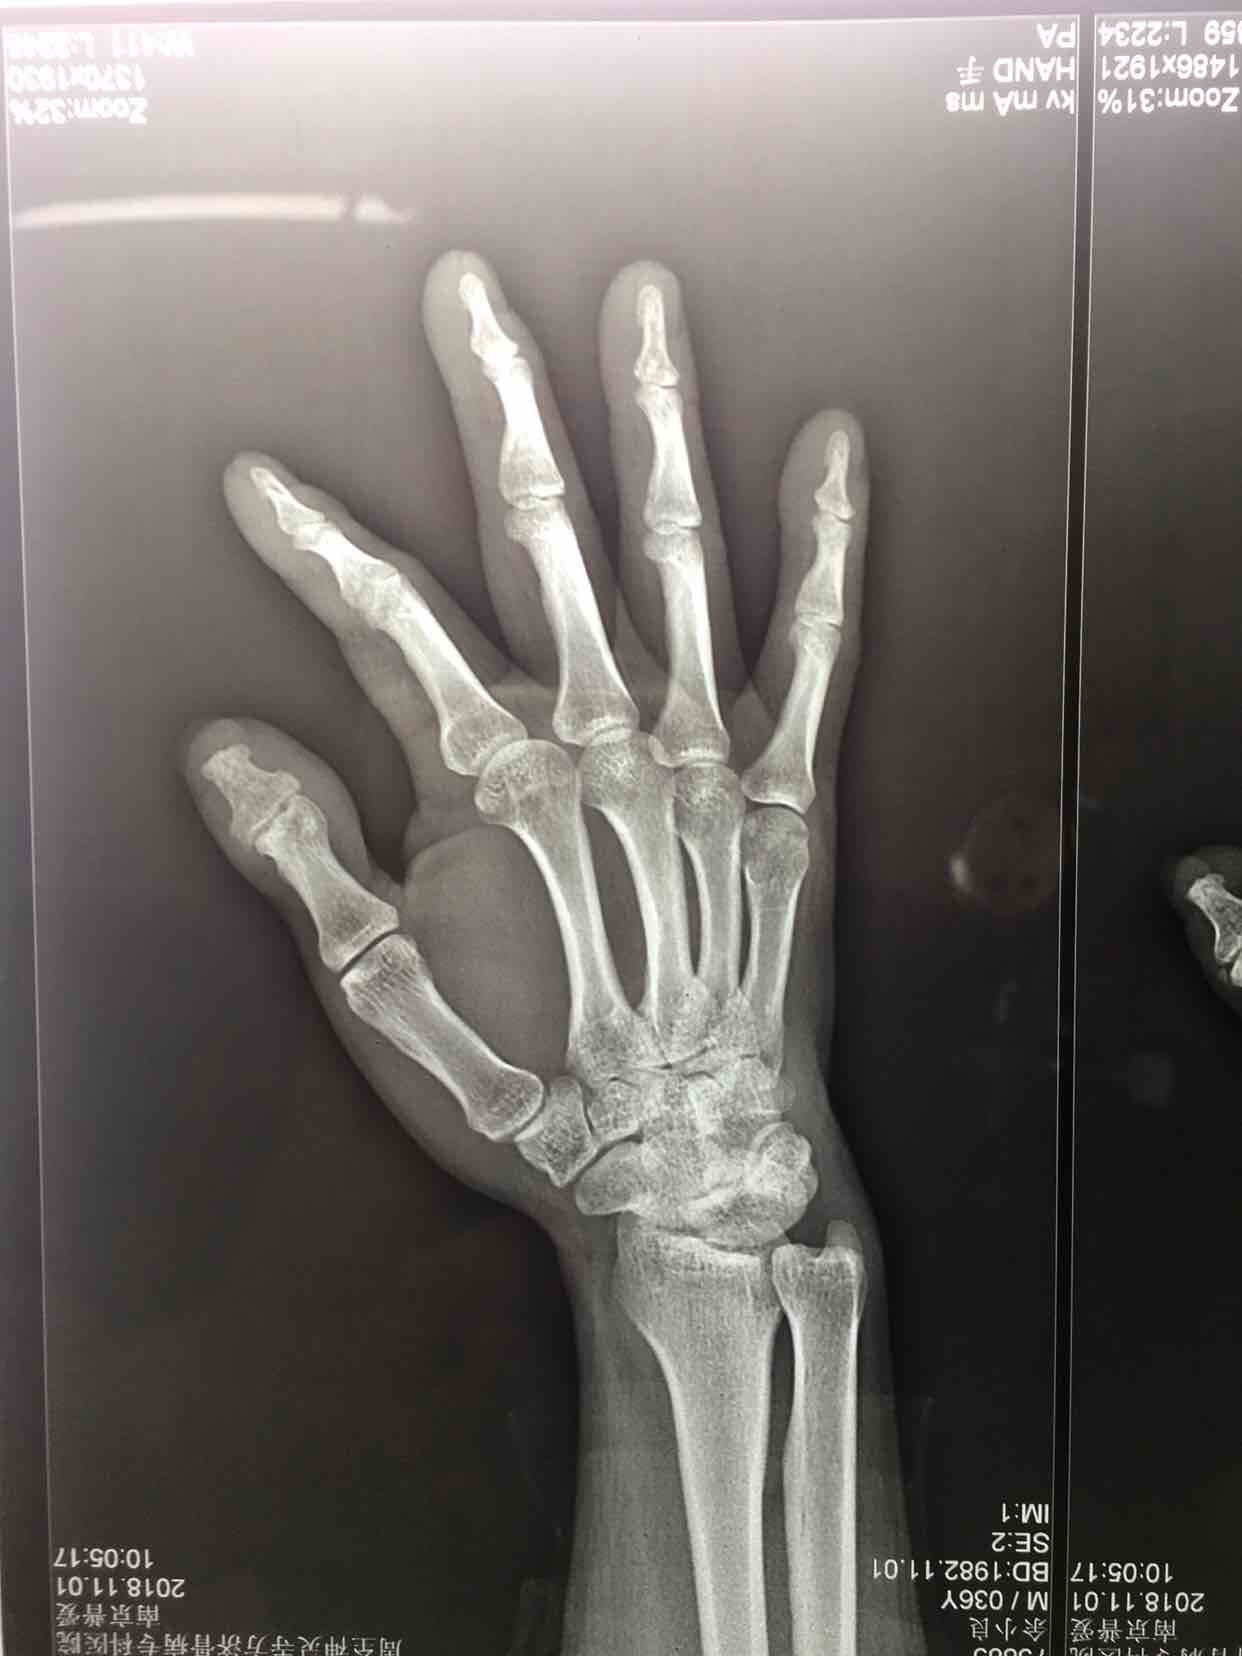

锤状指(切复内固定术)

锤状指

摔伤后右小指肿胀,畸形14天。既往身体健康,无特殊不良嗜好。

生命体征平稳,右小指肿胀,畸形,局部皮色皮温基本正常,伸指功能障碍,屈指正常,末梢血运感觉正常。

完善术前准备,在指神经阻滞麻醉下行切复内固定术,术后制动4-6周,预防感染等处理。